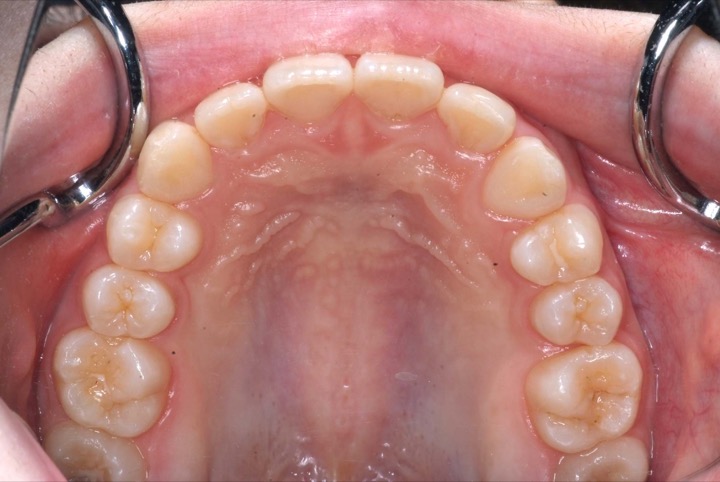

前期治療は、非抜歯の上、マウスピース型矯正装置(インビサライン・ファースト)で行いました。その後、歯列矯正用咬合誘導装置(マイオブレース)で舌位の改善を行いました。治療期間は5年1ヶ月でした。通院回数:37回。

歯列矯正を始めるに当たって、後戻り・失活・虫歯(歯周病)・歯根吸収・ブラックトライアングル・歯肉退縮・顎関節症などのリスクがあることを説明し、患者さんには十分ご理解頂いた上で治療を行いました(以下もご覧ください)。